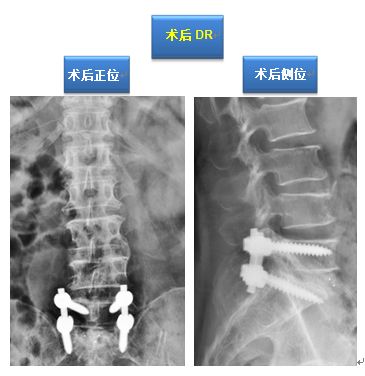

该手术在梁徳主任指导下由江晓兵副教授按照标准化流程顺利完成,将致压髓核进行了彻底摘除,神经压迫顺利解除。术后复查如下:

术后影像学提示可见L5/S1突出物已被完全摘除,神经减压良好。

治疗方案:后路L5/S1减压植骨融合内固定术

该手术在梁徳主任指导下由江晓兵副教授按照标准化流程顺利完成,将致压物进行了彻底摘除,神经压迫顺利解除,并进行植骨及钉棒系统内固定。术后复查如下:

手术后患者原有症状完全消除,但1个多月后,该患者来到门诊后询问我科江晓兵副教授:“为什么我做了手术后刀口周围会痛呢?”,在我科筋骨并重查体评估原则指导下,我们进行了仔细的触诊评估,发现手术切口周围有显著的筋膜肌肉粘连,这样的现象在部分患者中会发生,与术后伤口周围炎症反应有关,周围肌肉筋膜粘连会引起患者疼痛不适,有些患者术后长期伤口周围疼痛就是这样的机制。发现了病因解决起来就很容易,使用棍点手法治疗2次后,患者伤口周围变硬、粘连的筋膜肌肉恢复至正常状态,疼痛也完全消除了。